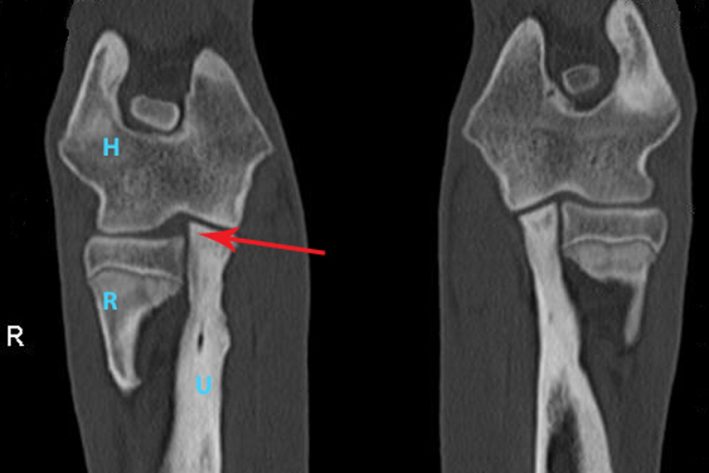

CT Inkongruenz Ellbogen

CT Aufnahme eines Hundes mit einer deutlichen Inkongruenz des rechten Ellbogengelenkes: Der Radius (R) hat einen deutlichen Abstand zum Humerus (H), weil die Ulna (U) zu lange ist.